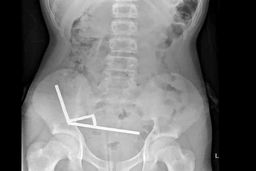

یک تیم پزشکی موفق شد یک گوشی تلفن همراه را از معده یک زندانی خارج کند که به مدت شش سال کامل در دستگاه گوارش او باقی…